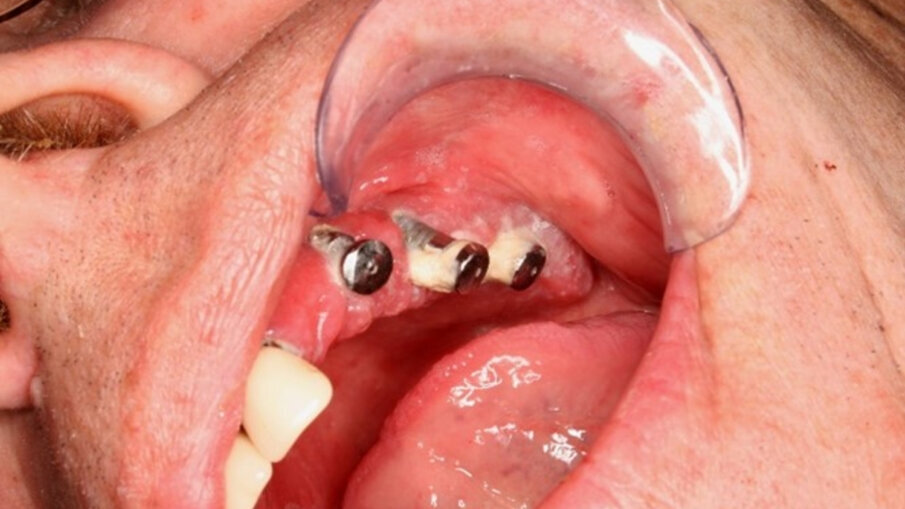

Na obrázcích 1a a 1b jsou zdokumentovány klinické případy periimplantitidy. Je na nich patrná hnisavá sekrece z „kapes“ kolem implantátů. Není již přítomný okrajový uzávěr z měkkých tkání a lze předpokládat úbytek kosti. Panuje vědecká shoda, že parodontitida nebo periimplantitida je způsobována nadměrnou bakteriální kolonizací gingivy v důsledku nevyhovující dentální nebo ústní hygieny. Je prokázáno, že progresivní parodontitida se častěji objevuje v celých rodinách. Přestože je její původ multifaktoriální, jsou důležité i genetické predispozice, protože některé geny byly izolovány jako jednoznačné rizikové faktory, včetně genu interleukin 1, proteináza 3 a katepsin. Jako další příčina a spouštěč periimplantitidy jsou stále důkladněji zkoumány nanočástice, které získají přístup do oblasti kosti během implantace prostřednictvím chirurgických nástrojů a samotného zavedení implantátu. Stále však neexistuje jednoznačně defi novaný standard nebo protokol léčby periimplantitidy. Vzhledem k velmi vysoké míře recidivy periimplantitidy po jednom roce, navzdory všem léčebným zákrokům (chirurgickým i nechirurgickým), nyní vyvstává otázka, zda periimplantitidu neudržují kovové částice uvolňující se z povrchu implantátu abrazí. Nechirurgická a chirurgická opatření zatím nesrovnávaly žádné studie.

Obr. 1. Klinická periimplantitida.